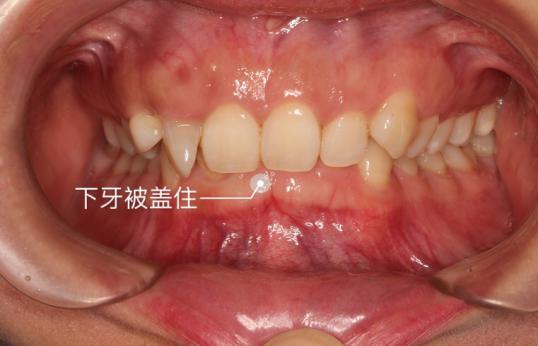

牙齿情况:深覆合,露龈笑,下巴后缩

还没戴牙套的时候,露龈笑,下巴短短的

我的牙齿情况:深覆合戴牙套的感受

科普一句:深覆合严重者易咬伤上牙龈,还易导致前牙的牙周炎疾病及面部关节疾病。齿深覆合影响人的外貌美观:牙齿深覆合会导致下面部变短,从而影响面容美观,不容小觑深覆合哦~牙齿矫正福利大放送杭州美莱口腔五周年庆